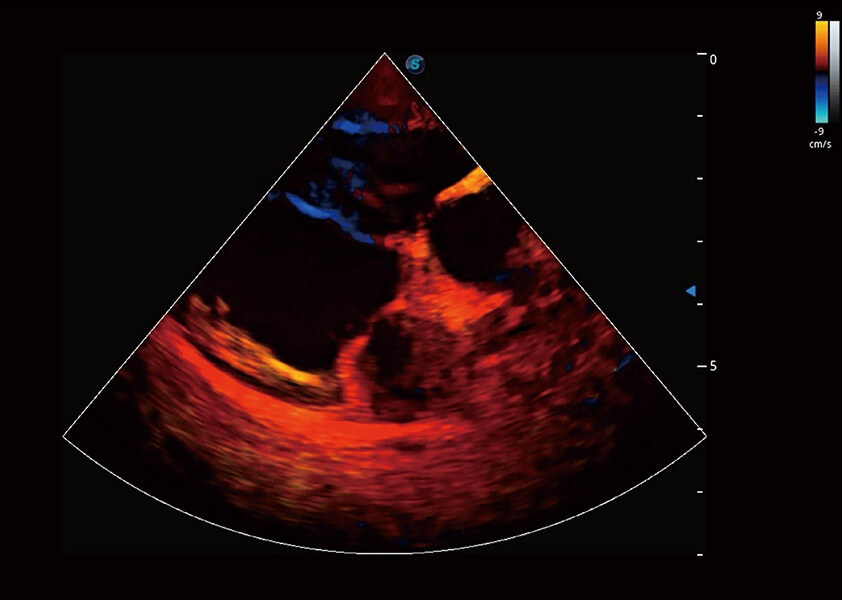

ProPet 60 作为一款高端台式动物超声设备,为动物医生的日常诊断提供了一系列贴合动物临床需求、解决临床实际问题的高级成像功能。凭借全系列高清探头,满足医生对腹部、心脏、生殖、浅表、肌骨等成像的所有需求,切实帮助您提升检查效率,提高诊断信心。

动物是人类最亲密的朋友和最值得信赖的伙伴。哈哈体育官网也一直致力于探索动物专用的超声影像解决方案。 全新推出的ProPet系列,是哈哈体育官网在动物超声影像智能化、专业化、精准化的一次跨越式革新。动物不能用言语来表述自己的不适,通过超声影像,ProPet系列搭建了动物医生与不同物种沟通的“桥梁”,为动物医生注入了“治愈之力”。